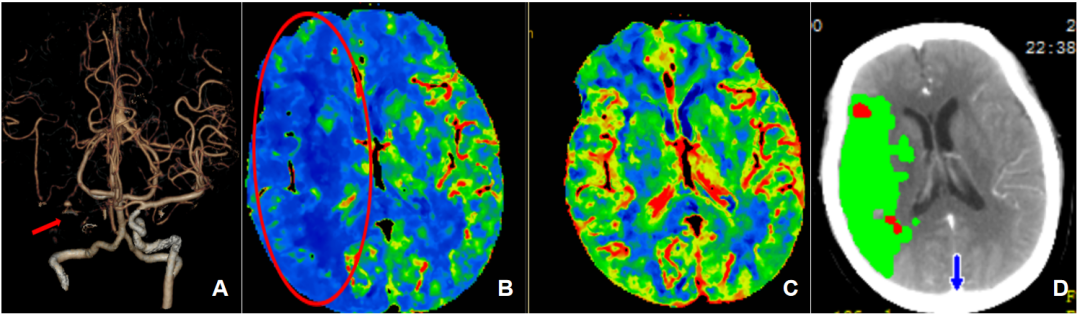

数日前,82岁的杨奶奶外出买菜时出现了两次左侧肢体麻木症状,由于很快缓解,她并未在意,但次日醒来后,症状又开始出现且未缓解。她被紧急送医并在外院被确诊为急性脑梗死,经治疗好转后,麻木症状却突然再次加重,同时还出现左侧肢体无力、说话不能连贯成句等情况。来到北京清华长庚医院急诊,神经内科一线医生张颖博立即为她启动脑卒中绿色通道,采用多模式CT评估,发现患者右侧颈内动脉血管完全闭塞(图1A)!

所幸的是,头颅灌注成像提示通过积极的血管开通治疗,闭塞的脑组织还有挽救的希望。绿道介入团队值班医师、神经内科主治医师王也快速到达现场查看病情,“因为距离上次脑梗死病变时间太近,无法使用溶栓药物,只能采用微创的介入动脉取栓技术,直接取出堵塞的血栓。”王也表示。

(A)头颈CTA检查提示右侧颈内动脉及右侧大脑中动脉未显影,提示右侧颈内动脉及大脑中动脉闭塞

(B,C)头颅CT灌注成像提示患者存在较大面积的缺血区域带(红圈所示)

(D)利用MIStar后处理软件精准定量缺血半暗带(绿色)及梗死核心(红色)体积